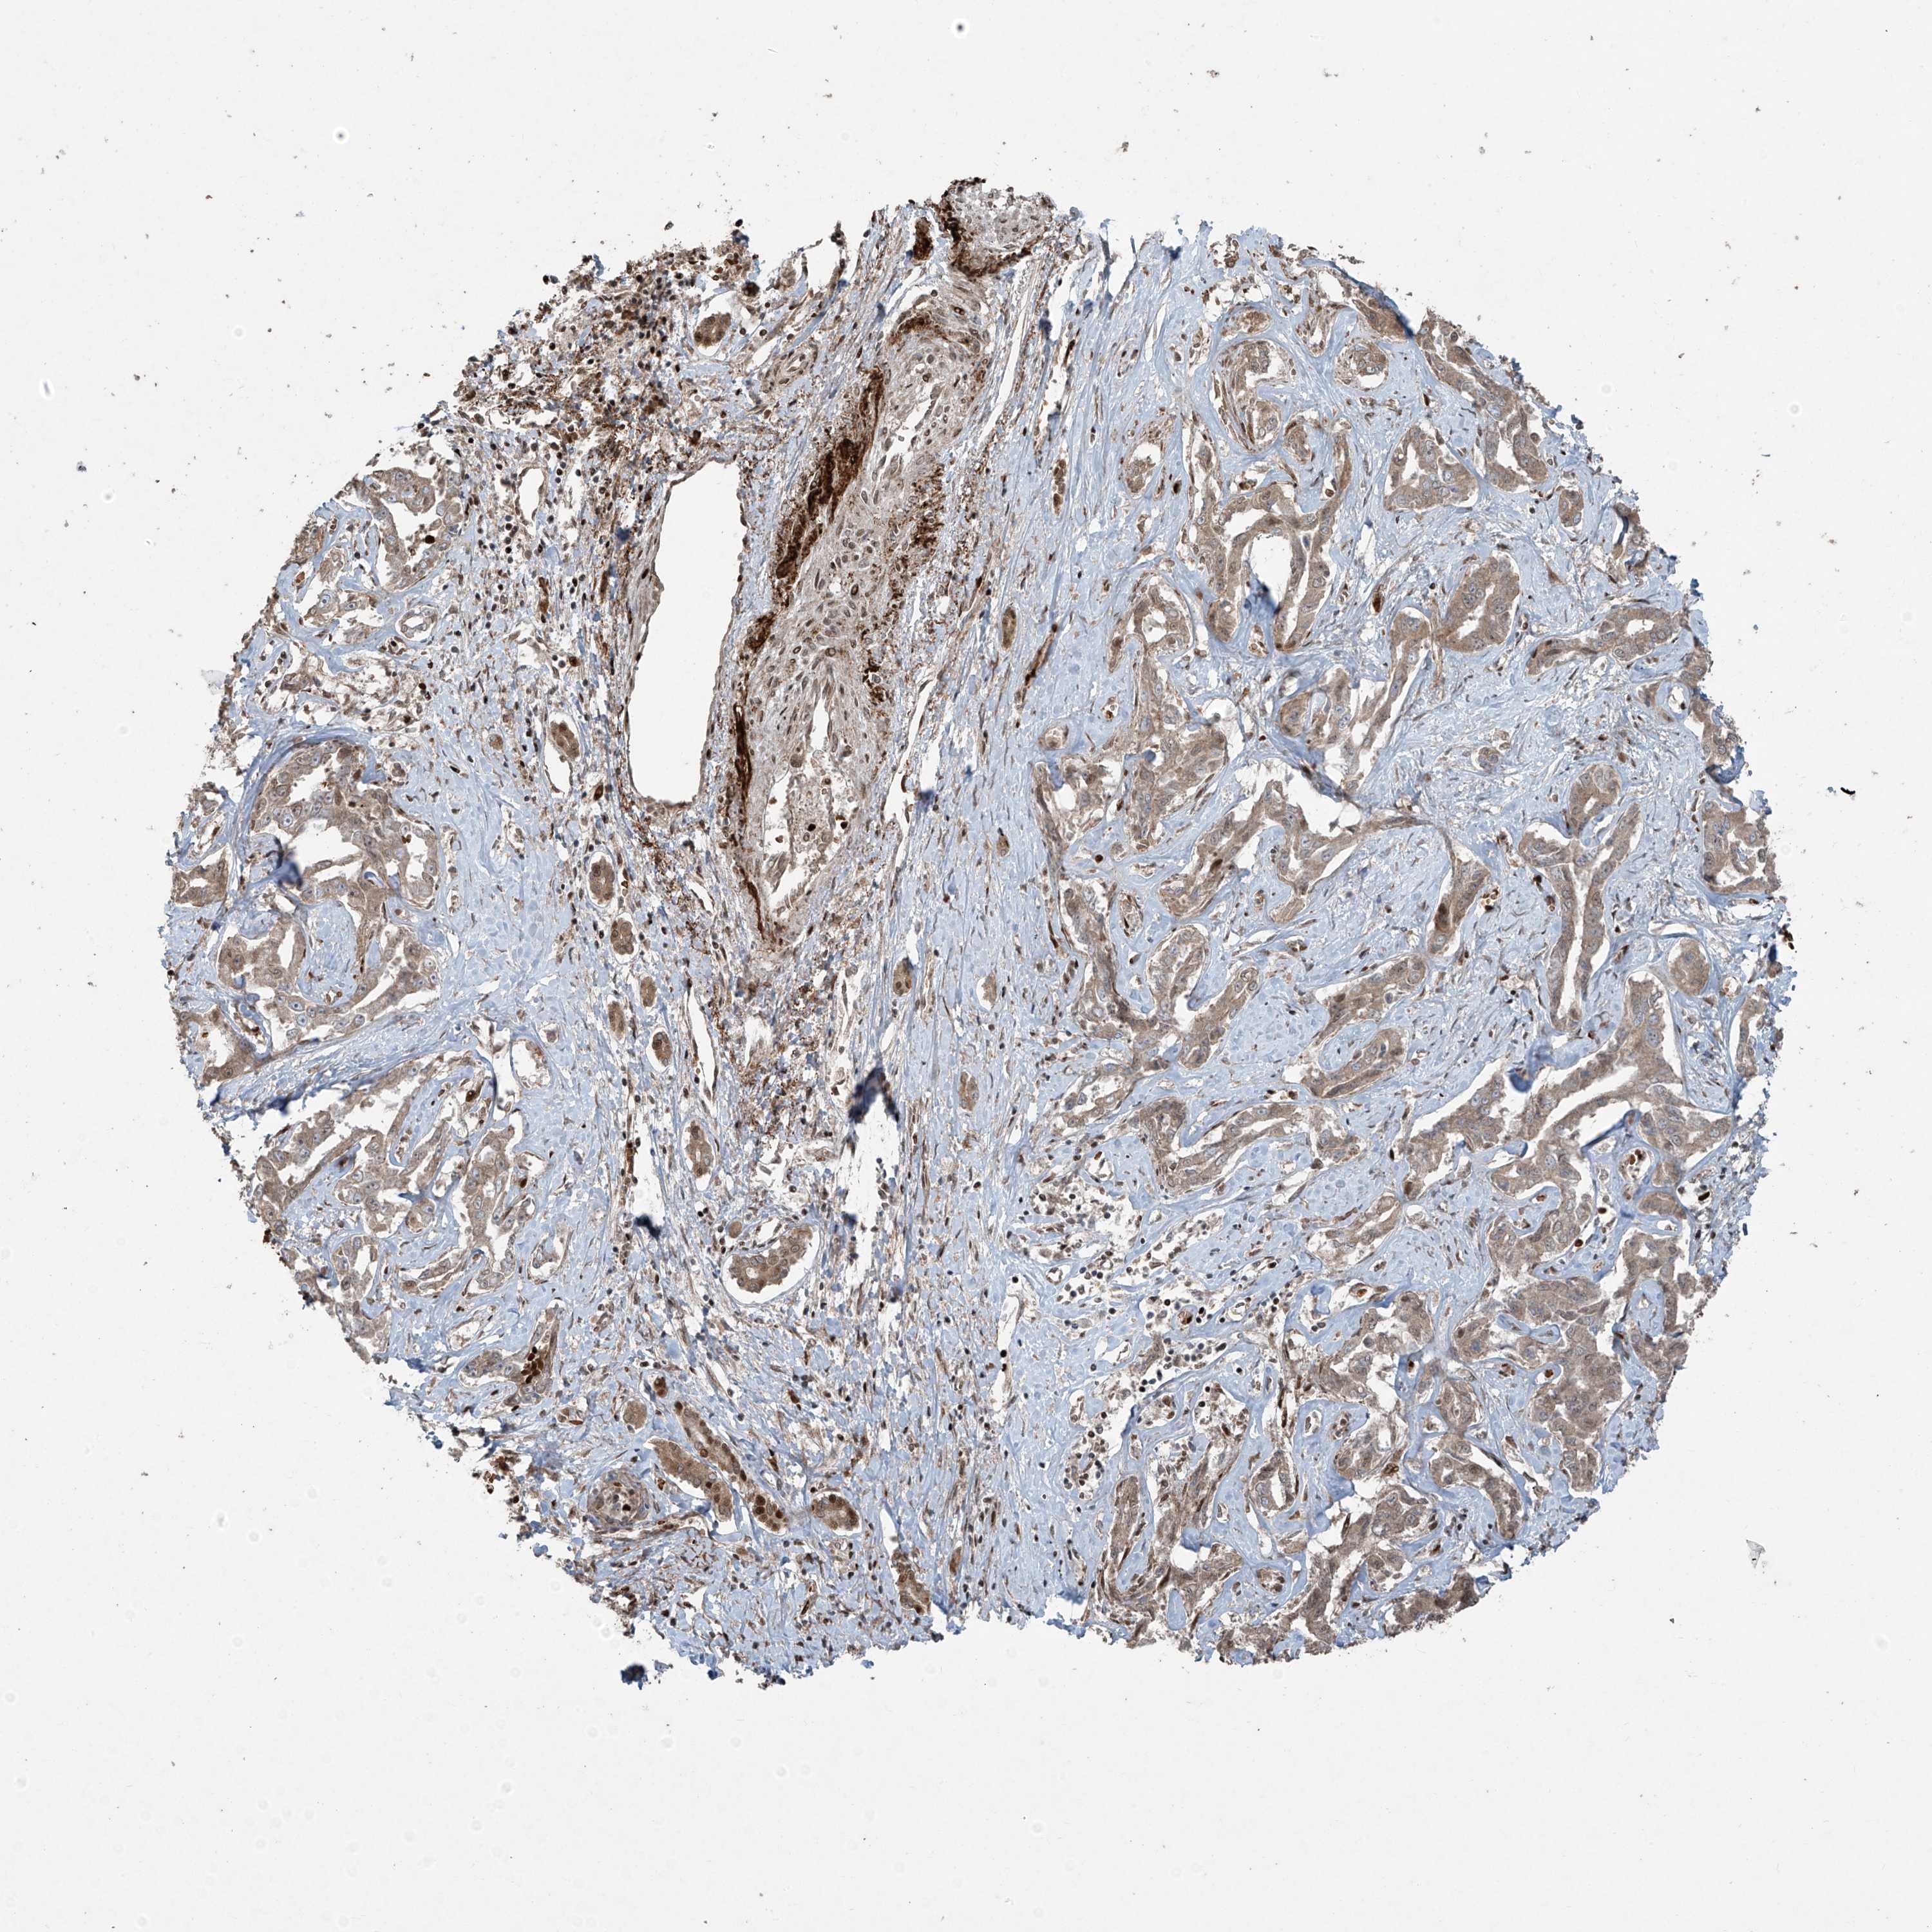

LIVER CANCER - Protein expressioni

A mouse-over function shows sample information and annotation data. Click on an image to view it in a full screen mode. Samples can be filtered based on level of antibody staining by selecting one or several of the following categories: high, medium, low and not detected. The assay and annotation is described here.

Note that samples used for immunohistochemistry by the Human Protein Atlas do not correspond to samples in the TCGA dataset.

Antibody stainingi

Antibody staining in the annotated cell types in the current human tissue is reported as not detected, low, medium, or high, based on conventional immunohistochemistry profiling in selected tissues. This score is based on the combination of the staining intensity and fraction of stained cells.

Each image is clickable and will lead to virtual microscopy that enables deeper exploration of all samples and also displays staining intensity scores, fraction scores and subcellular localization as well as patient and tissue information for each sample.

Antibody HPA035072

Staining

High

Medium

Low

Not detected

Intensity

Strong

Moderate

Weak

Negative

Quantity

>75%

75%-25%

<25%

None

Location

Nuclear

Cytoplasmic/membranous

Cytoplasmic/membranous,nuclear

Cholangiocarcinoma

Carcinoma, Hepatocellular, NOS